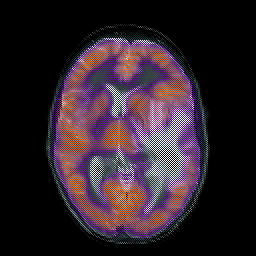

Metastatic bronchogenic carcinoma, overlay -- Slice #11

[Home][Help][Clinical] Slice 11